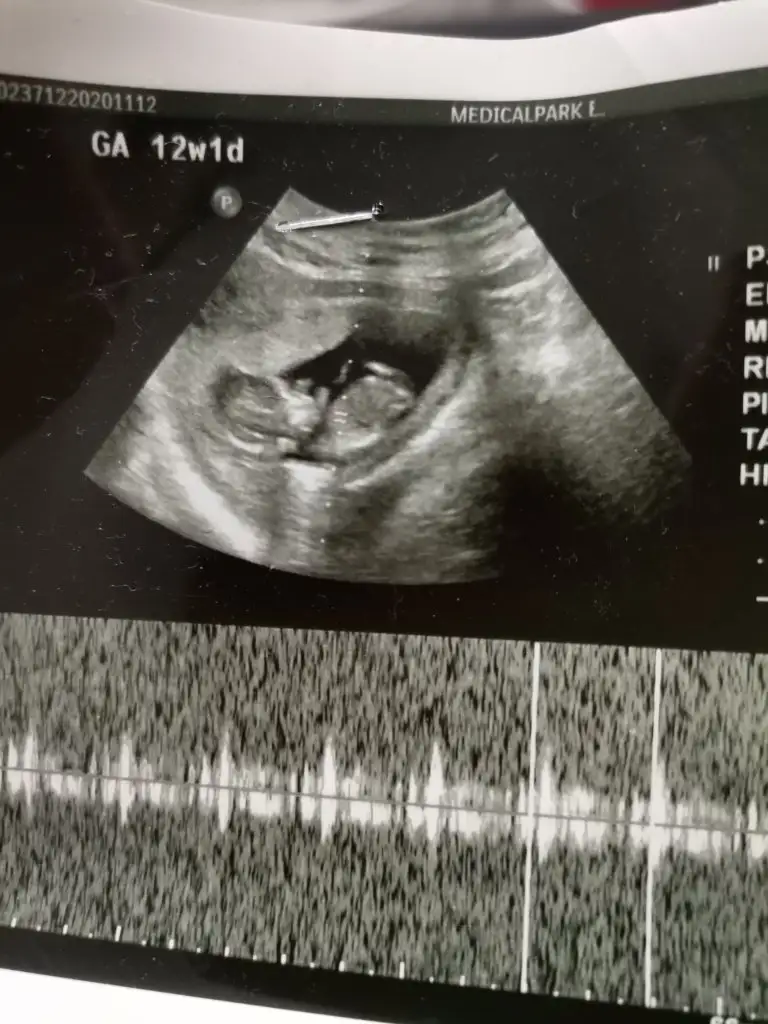

Benim içinde bir yorum yapar mısınız

Eklentiler

• IMG_20201209_163424.webp

IMG_20201209_163424.webp

48,3 KB · Görüntüleme: 66